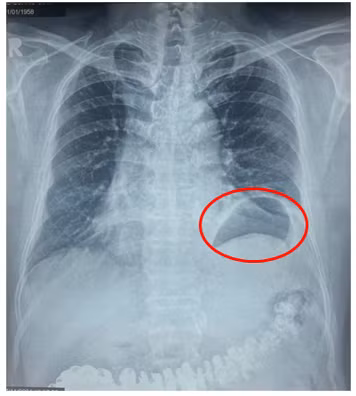

Cách lần nhập viện này khoảng 3 tháng, bệnh nhân L.Q.G. (66 tuổi, ngụ tại tỉnh Tây Ninh) xuất hiện tình trạng khó thở, thở hụt hơi khi gắng sức, vận động hoặc lên cầu thang. Điều này làm bệnh nhân G. không thể vận động thể lực mạnh và duy trì thói quen đi bộ tập thể dục. Tại lần khám sức khỏe gần nhất, kết quả chụp X-quang ghi nhận bệnh nhân G. có bất thường ở vùng phổi trái, nên đến bệnh viện chuyên khoa lồng ngực thăm khám và điều trị.

Thấy tình hình khó thở không thuyên giảm, bệnh nhân G. đến thăm khám tại Bệnh viện Bình Dân (TPHCM). Tại đây, các bác sĩ chẩn đoán bệnh nhân G. bị nhão hoành trái với hình ảnh vòm hoành trái nhô cao bất thường. Tình trạng này làm giảm thể tích lồng ngực trái, đây chính là nguyên nhân khiến ông bị khó thở khi gắng sức nhiều tháng nay mà ông không rõ nguyên nhân.

Để chẩn đoán bệnh nhão cơ hoành, liệt cơ hoành, các bác sĩ thường chỉ định người bệnh thực hiện chụp phim X-quang ngực và MSCT - scan ngực. Qua hình ảnh, các chuyên gia có thể thấy cơ hoành bị nâng lên cao hơn so với bình thường.